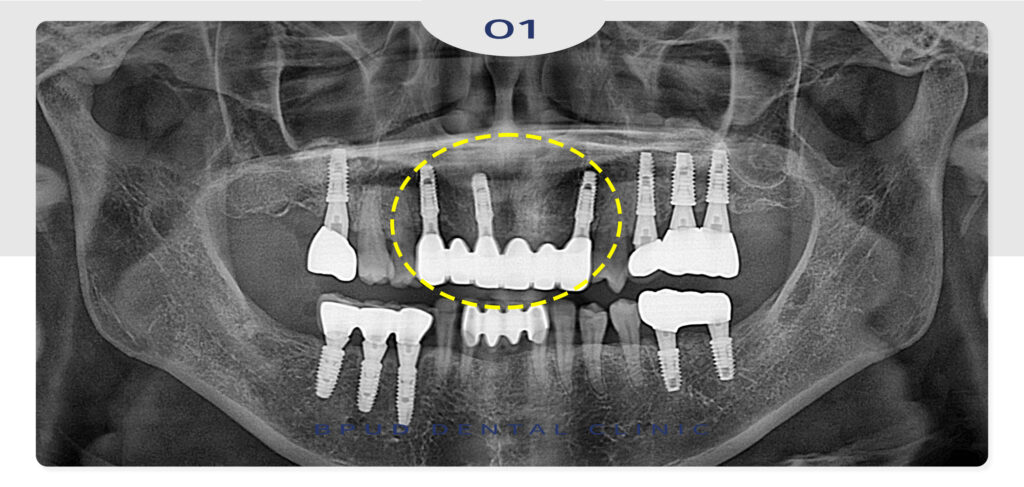

25.11.01

최종 보철물까지 완성한 모습입니다.

치료 기간도 길지 않고 심미적으로 만족하셨으며

아래쪽 앞니도 좋지 않으시다고 하시며

조만간 발치 후 임플란트를 진행하시기로

약속 하셨답니다!^^